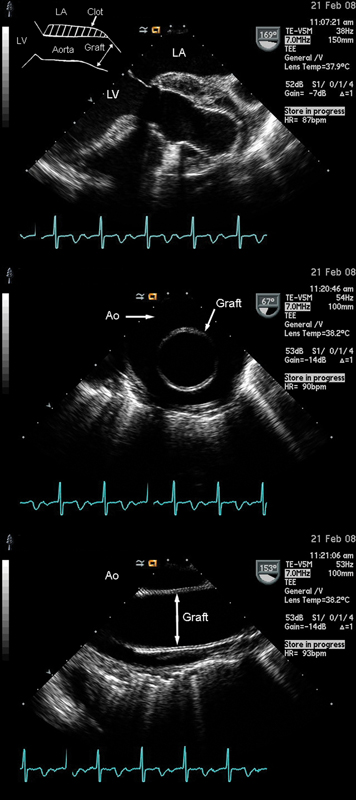

فحوصات تشخيصية لبعض امراض القلب والشرايين التاجية